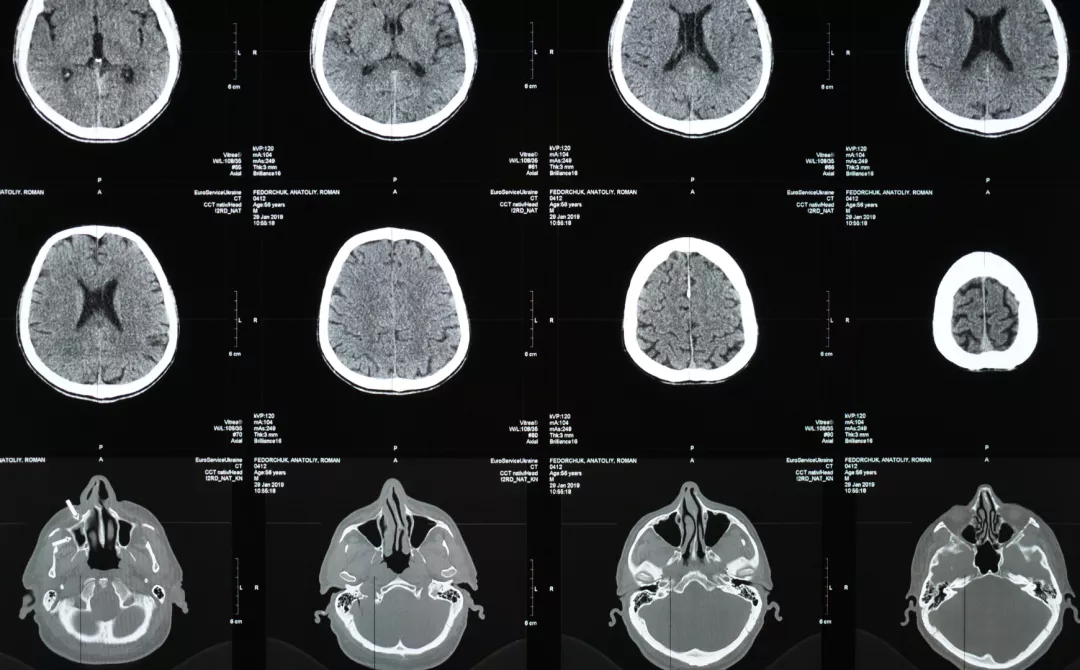

Illustration of brain MRI scans

Diagnosis